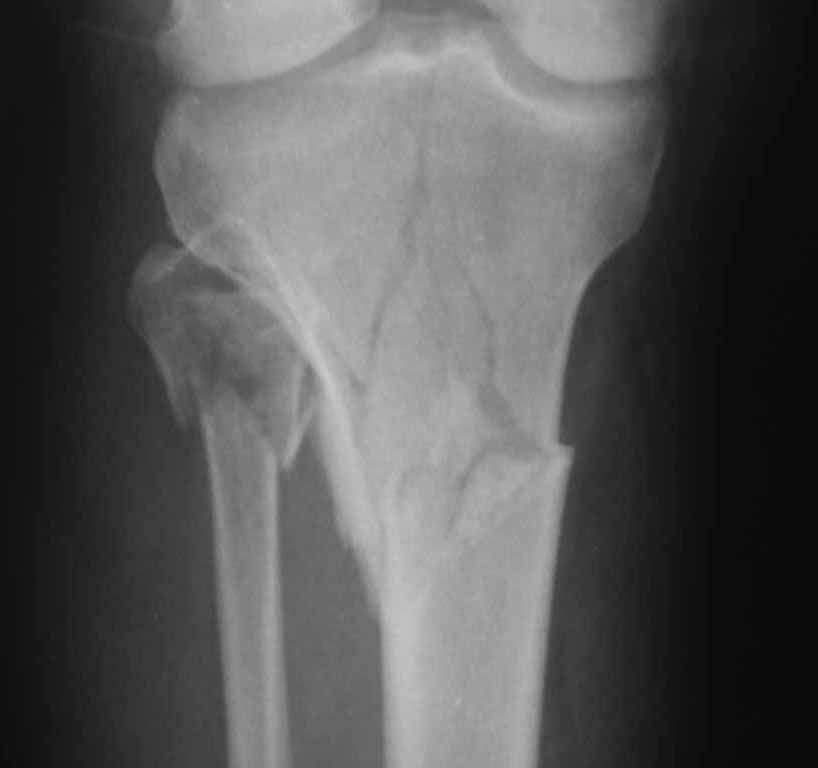

Мужчина 40 лет получил закрытый внутрисуставной перелом верхней трети костей правой голени в результате ДТП (см. рентгенограммы). Какой фиксатор подошел бы для данного перелома понятно, однако у пациента имеется по передне-наружной поверхности верхней трети голени ссадина и участок некроза кожных покровов (см. фото), поэтому латеральная мыщелковая пластина не подойдет, а медиальных пластин у фирм-производителей нет. Пациент может приобрести современный имплант, но какой….???? Слышал, что некоторые ставят, например, левую латеральную мыщелковую пластину по медиальной поверхности правой голени – работает ли это? Каким фиксатором и каких фирм прооперировали бы Вы??? Заранее СПАСИБО!!!